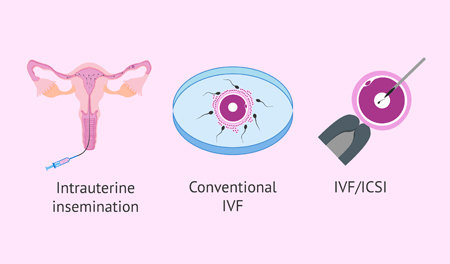

Advanced reproductive procedures using state-of-the-art technology.